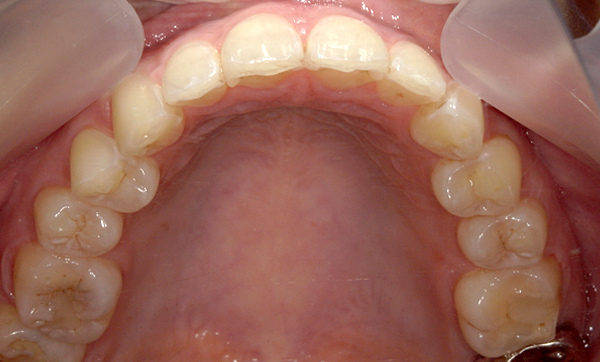

症例_009 「上下の前歯」症例

治療期間:7ヶ月金額:54万円+税20代女性捻転歯一部の反対咬合前歯のガタガタ

Before | After |

---|---|